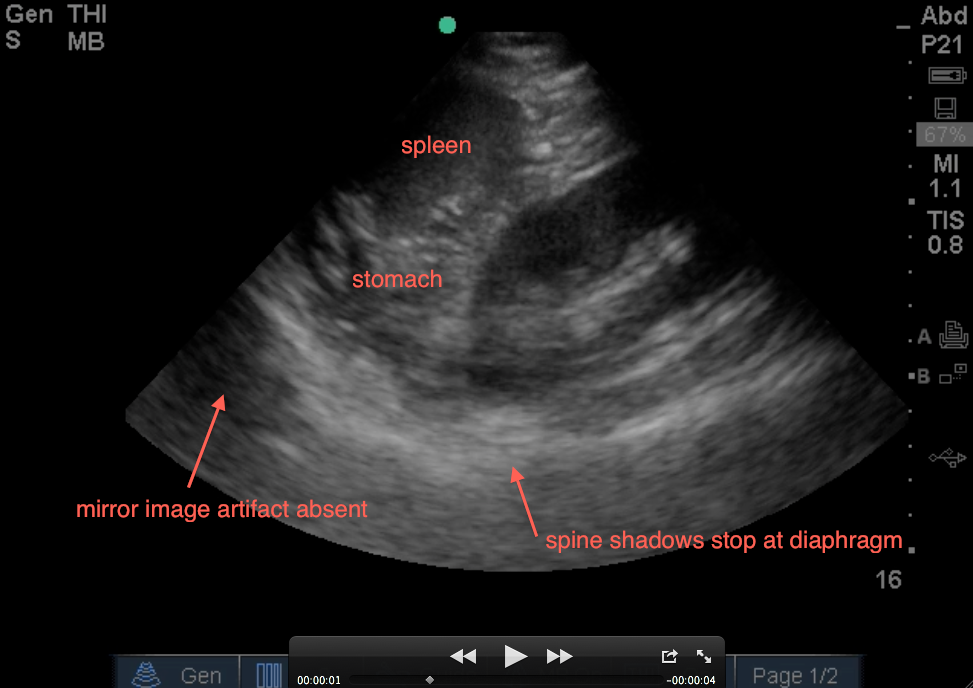

1. Evaluate above the diaphragm…. to evaluate for intrathoracic free fluid. This may involve having to increase your depth while you slowly fan your probe anterior to posterior (from 13cm to 16cm – you dont usually need to go 19cm unless it’s a huge spleen). The patient’s breathing will also help you as you will notice the bright white (echogenic) linear diaphragm which hugs the spleen will move (right and left) on your screen with every breath. Having the patient take a deep breath and holding it, will allow you better visualization if a rib shadow is in your way. A mirror image of the spleen may be seen above the diaphragm (a normal artifact that occurs when ultrasound passes through structures of varying densities and then through air (lung). However, in the LUQ, If no mirror image, it may not mean free fluid, especially if the stomach is in your view. If the area above the diaphragm is truly anechoic (black) without Stomach Sabotage – that’s fluid in the thoracic cavity! The spine sign will also help you evaluate for free intra-thoracic fluid, as the spine and it’s shadowing normally stops once it hits the diaphragm when visualizing on the screen from right to left (air is the enemy of ultrasound!). But if there is fluid in the thoracic cavity, you will see the spine continue to traverse past the diaphragm up into the thoracic area (fluid is the lover of ultrasound!).